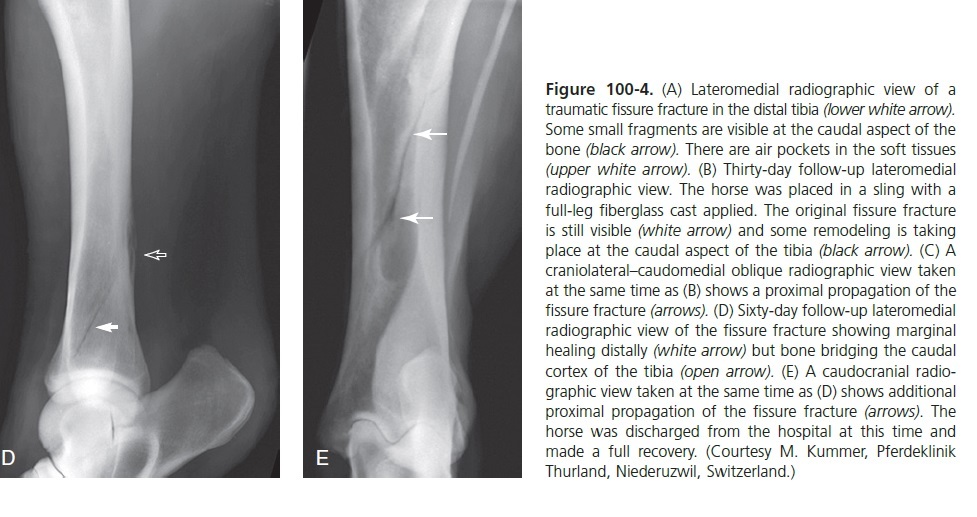

What causes fissure fractures of the tibia in horses?

Incomplete and nondisplaced complete fractures normally are candidates for:

Conservative therapy toreduce the likelihood of displacement secondary to forces experienced duringstanding up. In these case the sling can be useful.

**minimum 3-4 months** During the last **3****0 days of confinement a program of gradually increased **hand walkingis recommended and then access to free paddock. An additional 30 days of paddock exercise is recommended too.

Figure 100-8. Lateromedial (A) and caudocranial (B) radiographic views of a spiral comminuted displaced midshaft tibial fracture in an adult horse.

30

Figure 100-8. Lateromedial (A) and caudocranial (B) radiographic views of a spiral comminuted displaced midshaft tibial fracture in an adult horse. Caudocranial (C) and lateromedial (D) radiographic views of the repaired fracture using two interfragmentary 4.5-mm cortex screws inserted in lag fashion and two staggered broad 4.5-mm DCPs, 3 weeks after surgery.